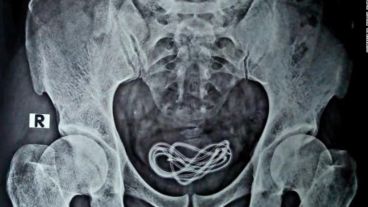

Fue en ese momento que una radiografía reveló que el hombre tenía un cable de cargador de 60 centímetros de largo dentro su vejiga, el cual fue insertado a través de su uretra, el tubo que va desde el pene a la vejiga. “Luego hice una incisión allí y saqué el cable, que en realidad era un cable de cargador de más de 60 centímetros de largo”, dijo Islam a CNN.